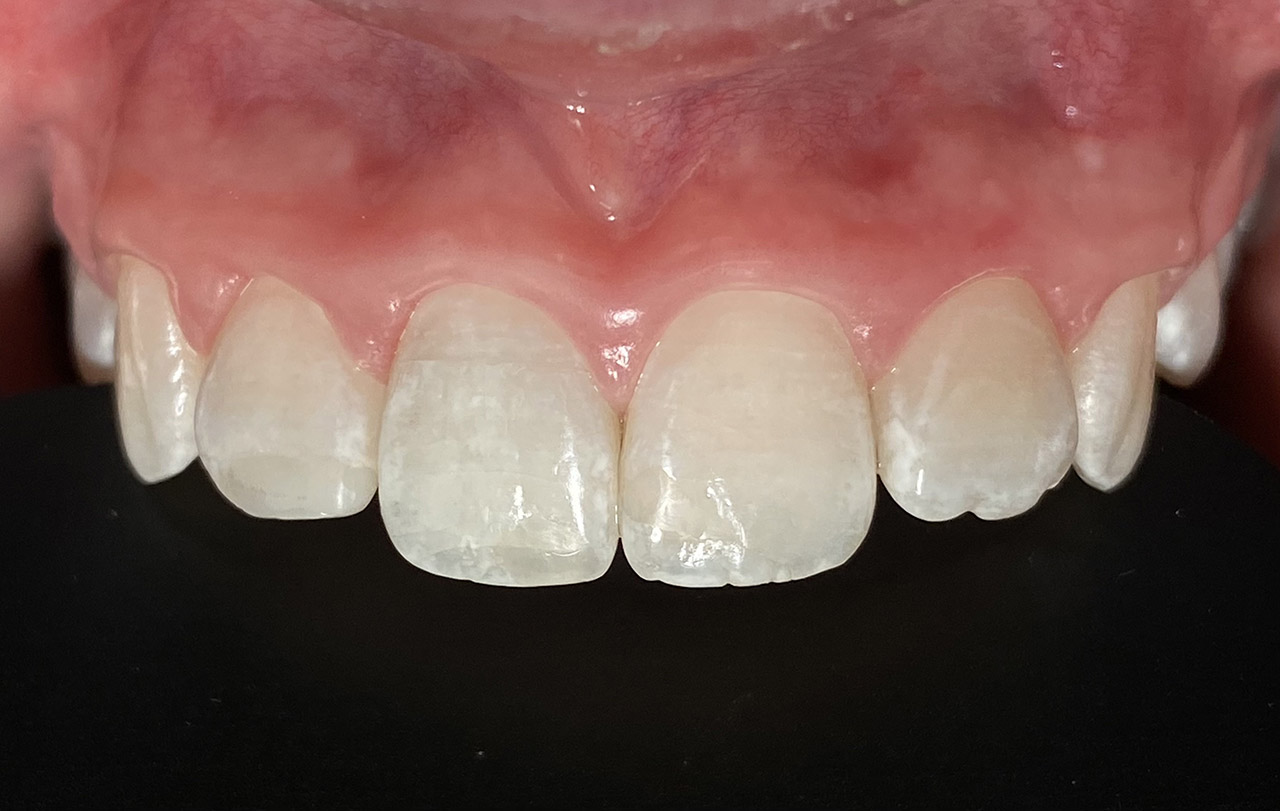

Internes und Externes Bleaching (Bleichen):

Nach Unfall mit E-Scooter unbefriedigendes Ergebnis der Erstversorgung (alio loco). Therapievorschlag: Stiftzähne?

Unsere minimalinvasive Therapie: Revision der Wurzelbehandlungen, danach internes und externes Bleaching, adhäsive Kunststoffüllungen in Schichttechnik. (Titel meiner Diplomarbeit 2003 “Die Vermeidung von Extraktion und Wurzelspitzenresektion durch zeitgemässe Endodontie in der Privatpraxis”)